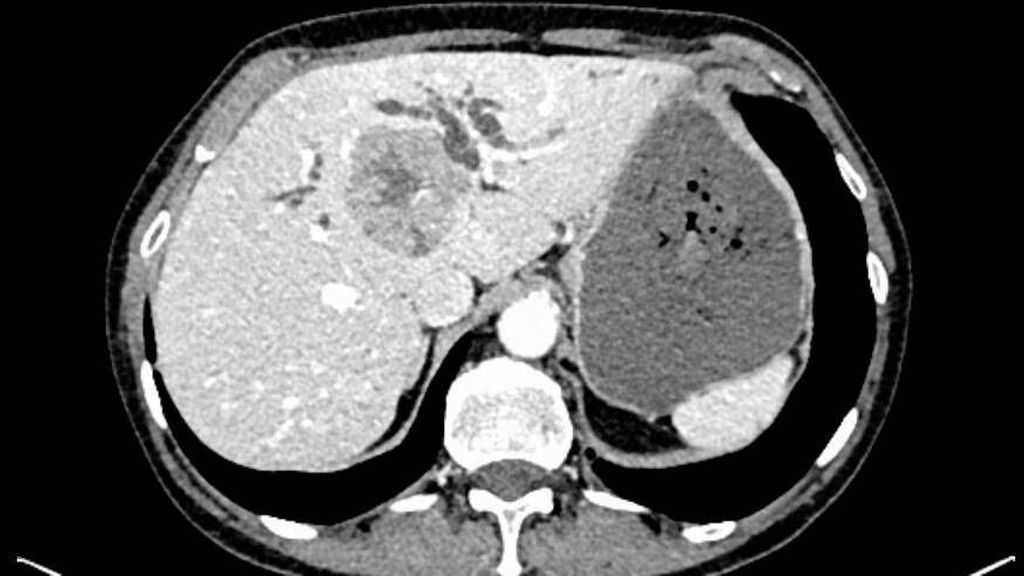

Die initiale CT zeigte eine bis zu 6cm große Raumforderung, ausgehend von der Hepatikusgabel, mit zentraler Infiltration des Leberparenchyms, suspekten Lymphknoten im Leberhilus und retroperitoneal, deutlich dilatierten intrahepatischen Gallengängen sowie Umscheidung und Infiltration des linken Pfortaderastes, jedoch ohne Thrombose. Der Befund war hochverdächtig auf einen cholangiozellulären Tumor. Die histologische Aufarbeitung einer Punktionsbiopsie ergab jedoch ein gering differenziertes, hiläres hepatozelluläres Karzinom (WHO 2019: G3). Angesichts des bildgebenden Befundes und des ebenfalls erhöhten Ca19-9 stand der Verdacht auf einen Mischtumor im Raum.

Bildgebend können sich Mischtumoren wie ein HCC-iCCA-Gemisch imponierend darstellen, wie ein typisches HCC oder aber ein typisches iCCA aussehen oder sich unspezifisch darstellen. Bildgebende Hinweise auf Mischtumoren bestehen bei verschiedenartigem Kontrastmittelverhalten innerhalb eines Tumors (im Verlauf zunehmende Anreicherung, Anreicherung mit Wash-out, Anreicherung ohne Wash-out oder Hypovaskularisierung), vaskulärer Invasion und Gallengangsbeziehungen. Die Kombination erhöhter Tumormarker (AFP und Ca19-9) kann einen Hinweis liefern, ist aber nicht beweisend.